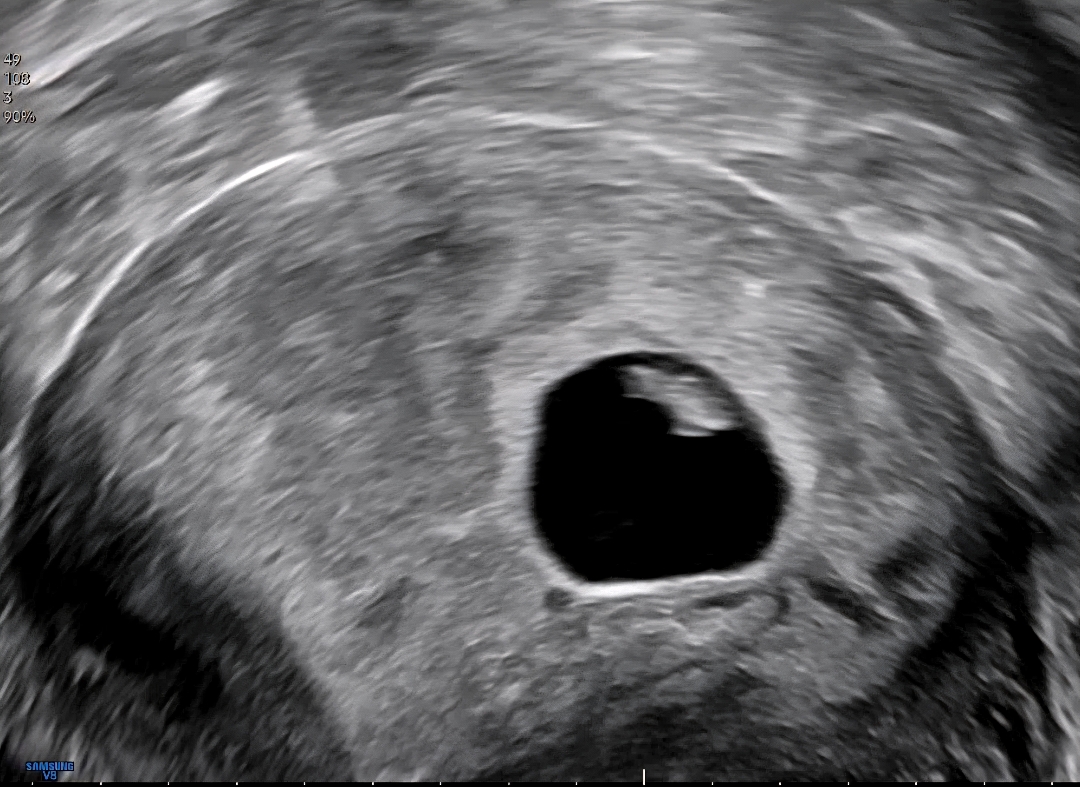

초음파

3일만에 이렇게 커졌네영 원래 아기집바뀌고 배아위치도 달라지는건가요?!